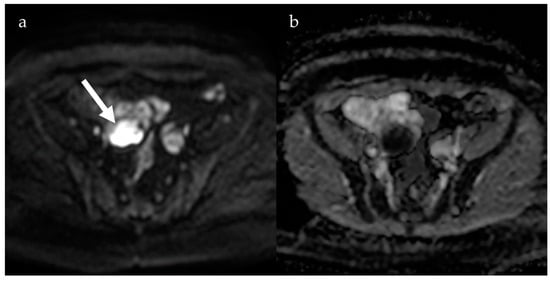

2.1. Endometrioma

4. Diffusion-Weighted Imaging

- Busard, M.P.H.; Mijatovic, V.; van Kuijk, C.; Bos, I.P.D.; Hompes, P.; van Waesberghe, J. Magnetic resonance imaging in the evaluation of (deep infiltrating) endometriosis: The value of diffusion-weighted imaging. J. Magn. Reson. Imaging 2010, 32, 1003–1009. [Google Scholar] [CrossRef] [PubMed]

- Balaban, M.; Idilman, I.S.; Toprak, H.; Unal, O.; Ipek, A.; Kocakoc, E. The utility of diffusion-weighted magnetic resonance imaging in differentiation of endometriomas from hemorrhagic ovarian cysts. Clin. Imaging 2015, 39, 830–833. [Google Scholar] [CrossRef] [PubMed]

- Moteki, T.; Horikoshi, H.; Endo, K. Relationship between apparent diffusion coefficient and signal intensity in endometrial and other pelvic cysts. Magn. Reson. Imaging 2002, 20, 463–470. [Google Scholar] [CrossRef]